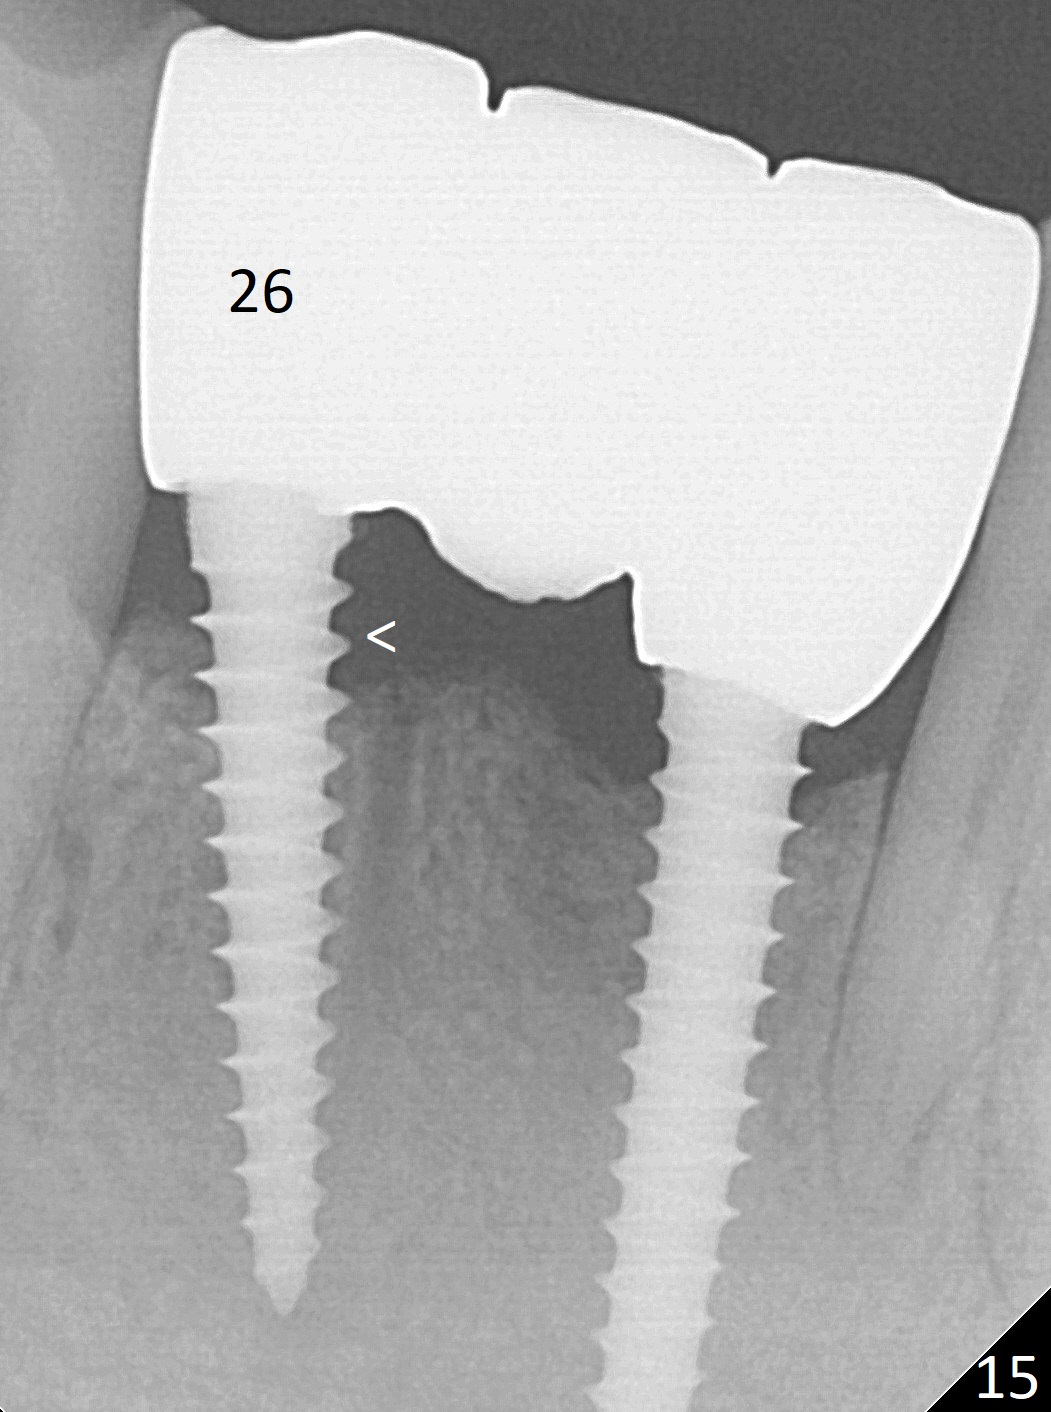

Fig.7 shows these two one piece implants immediately prior to cementation of the FPD (Fig.8). They are much more parallel to each other after prep, as compared to Fig.6. Fig.9 shows apparent bone growth around #24 implant (at the crest) 6,9 months post cementation and surgery, respectively. Orthodontic treatment will incorporate the fixed partial denture. Fig.10 shows that bone grows coronally (arrow) to cover 3 threads (from #6 thread to #3) at the site of #24 one year after functioning. There is mild buccal gingival infection involving #26 retainer. Preop CBCT is reviewed to determine whether it is related to potential thread exposure. It appears that at the sites of #24 (Fig.13,14) and 26 (Fig.11,12), 2.5 mm implant is more appropriate for the narrow ridge than 3.0 mm one. In fact, periimplantitis develops at #26 two years of absence of perio maintenance (because of atrial fibrillation with blood thinner; Fig.15, 3 years 7 months post cementation). Periimplantitis persists 4.5 months later. Although water pik is purchased, it is not used often because of low blowing force. If needed, remove the FPD atraumatically. Unwind the implant, clean the coronal threads with Titanium brush or remove the exposed threads and replant the implant with bone graft.